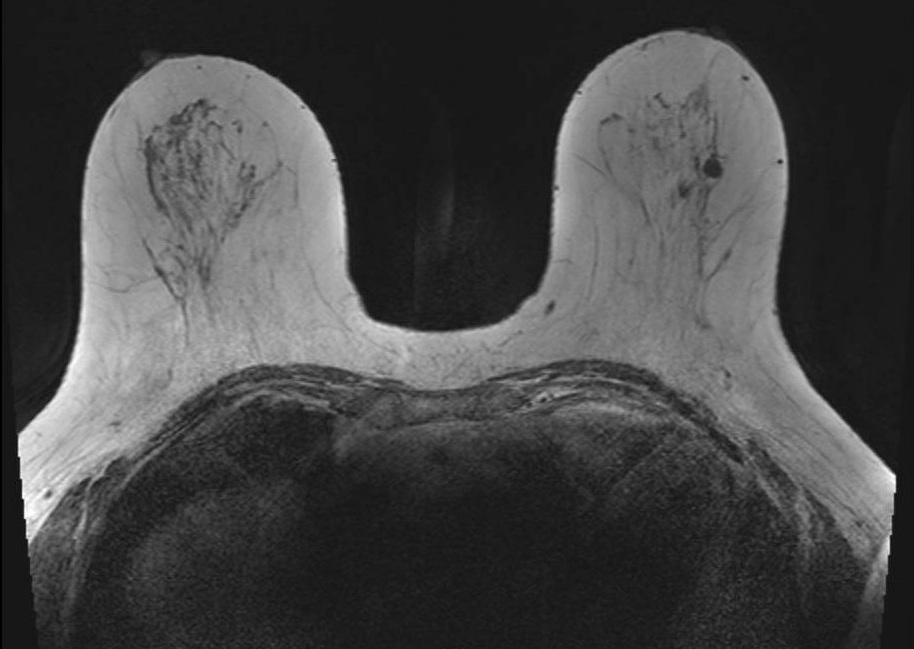

Geometric Distortion

Geometric distortion on T2-weighted imaging. Axial T2-weighted image windowed to display the full extent of the reconstructed FOV demonstrates curvilinear bowing at the image corners. This appearance reflects the scanner's gradient nonlinearity correction algorithm, which remaps peripheral voxels to compensate for inherent gradient field deviation at the extremities of the imaging volume. While the correction reduces geometric error centrally, residual distortion and interpolation artifacts remain visible at the periphery, which can affect tasks that require precise geometric accuracy.